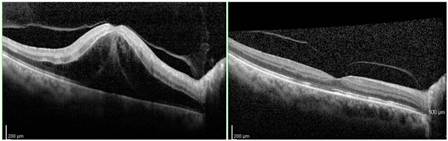

Optical Coherence Tomography

Optical coherence tomography (OCT) is useful in the assessment of macular edema, and particularly in monitoring its course, especially with treatment of the edema.

Typically, the OCT shows cystoid macular edema with or without subfoveal fluid. Epiretinal membrane or vitreomacular traction may also be evident.

In patients with recent-onset CRVO, OCT can detect areas of presumed ischemic edema in the plexiform layer due to ischemia of intermediary neurons within the inner nuclear and inner plexiform layers[10].

If macular edema is present, anti-VEGF therapy is the current first-line treatment. In the beginning, monthly follow-up is needed with OCT for monitoring treatment response and continued therapy to minimize the macular edema. Over time, the injection intervals may be adjusted, depending on treatment response.